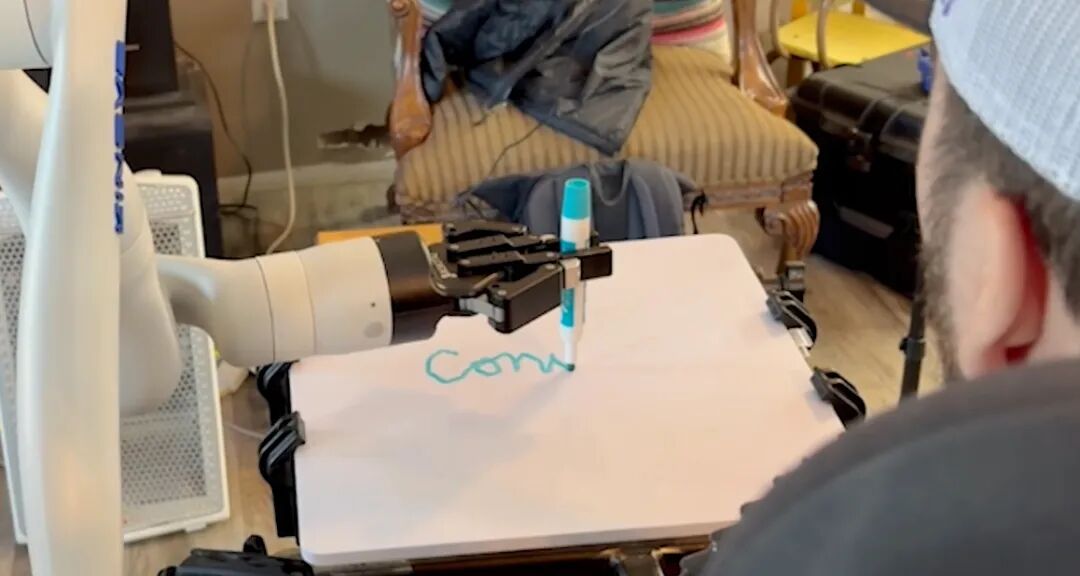

彭雷:不管哪种脑机接口,最终都得回到临床上,看对什么样的患者有什么样的价值。电学的脑机接口,现在分成了“读”、“写”两个路线。“读”的脑机接口更多的是做运动解码跟语言解码。脑虎也做到了这样非常好的一些demo。大家针对的患者,像渐冻症,像高危截瘫,通过脑机接口,让他通过解码的方式,能控制鼠标,那这样的患者就获得了Digital Autonomy(数字自主权)。这是在电学脑机接口的时候主要的适应症。

图片来源:neuralink.com